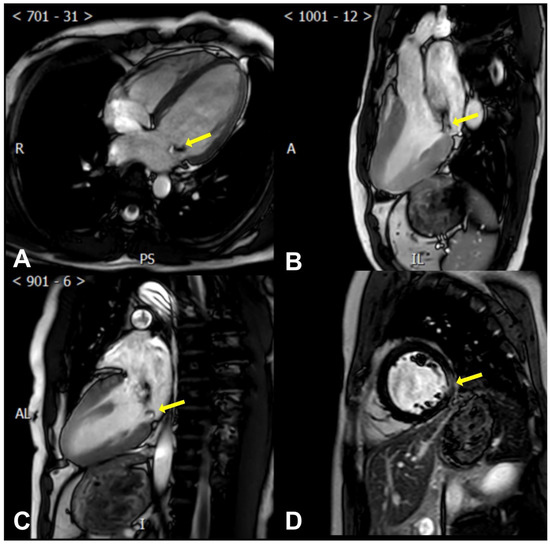

CMR allows for precise measurements of the left ventricular mass and end-diastolic thickness. This encompasses gauging the ratio of the basal-to-mid left ventricular wall thickness, identifying MAD and systolic curling (presence or absence) and quantifying it, measuring the mitral valve leaflet length, leaflet diastolic thickness, annulus diameter (at end-diastole and end-systole in both inter-commissural and anteroposterior aspects), and prolapse distance [89,90] (Figure 3).

Figure 3.

Cardiac magnetic resonance findings of AMVP. (A) The posterior mitral leaflet prolapse (yellow arrow) is seen in a perspective resembling the apical four-chamber view; (B) The posterior mitral leaflet prolapse (yellow arrow) is seen in a perspective resembling the apical three-chamber view; (C) The posterior mitral leaflet prolapse (yellow arrow) is seen in a perspective resembling the apical two-chamber view; (D) Late gadolinium enhancement of the left ventricular lateral wall (yellow arrow) is seen in a perspective resembling the parasternal short axis view.

More importantly, CMR can help determine the myocardial composition and identify VAs’ specific risk factors, assess myocardial fibrosis/scar, describe its location, and quantify it [91]. Late gadolinium enhancement (LGE) [92,93] sequences reveal patchy macroscopic fibrosis, while T1 mapping identifies diffuse fibrosis at a microscopic level (Figure 3).